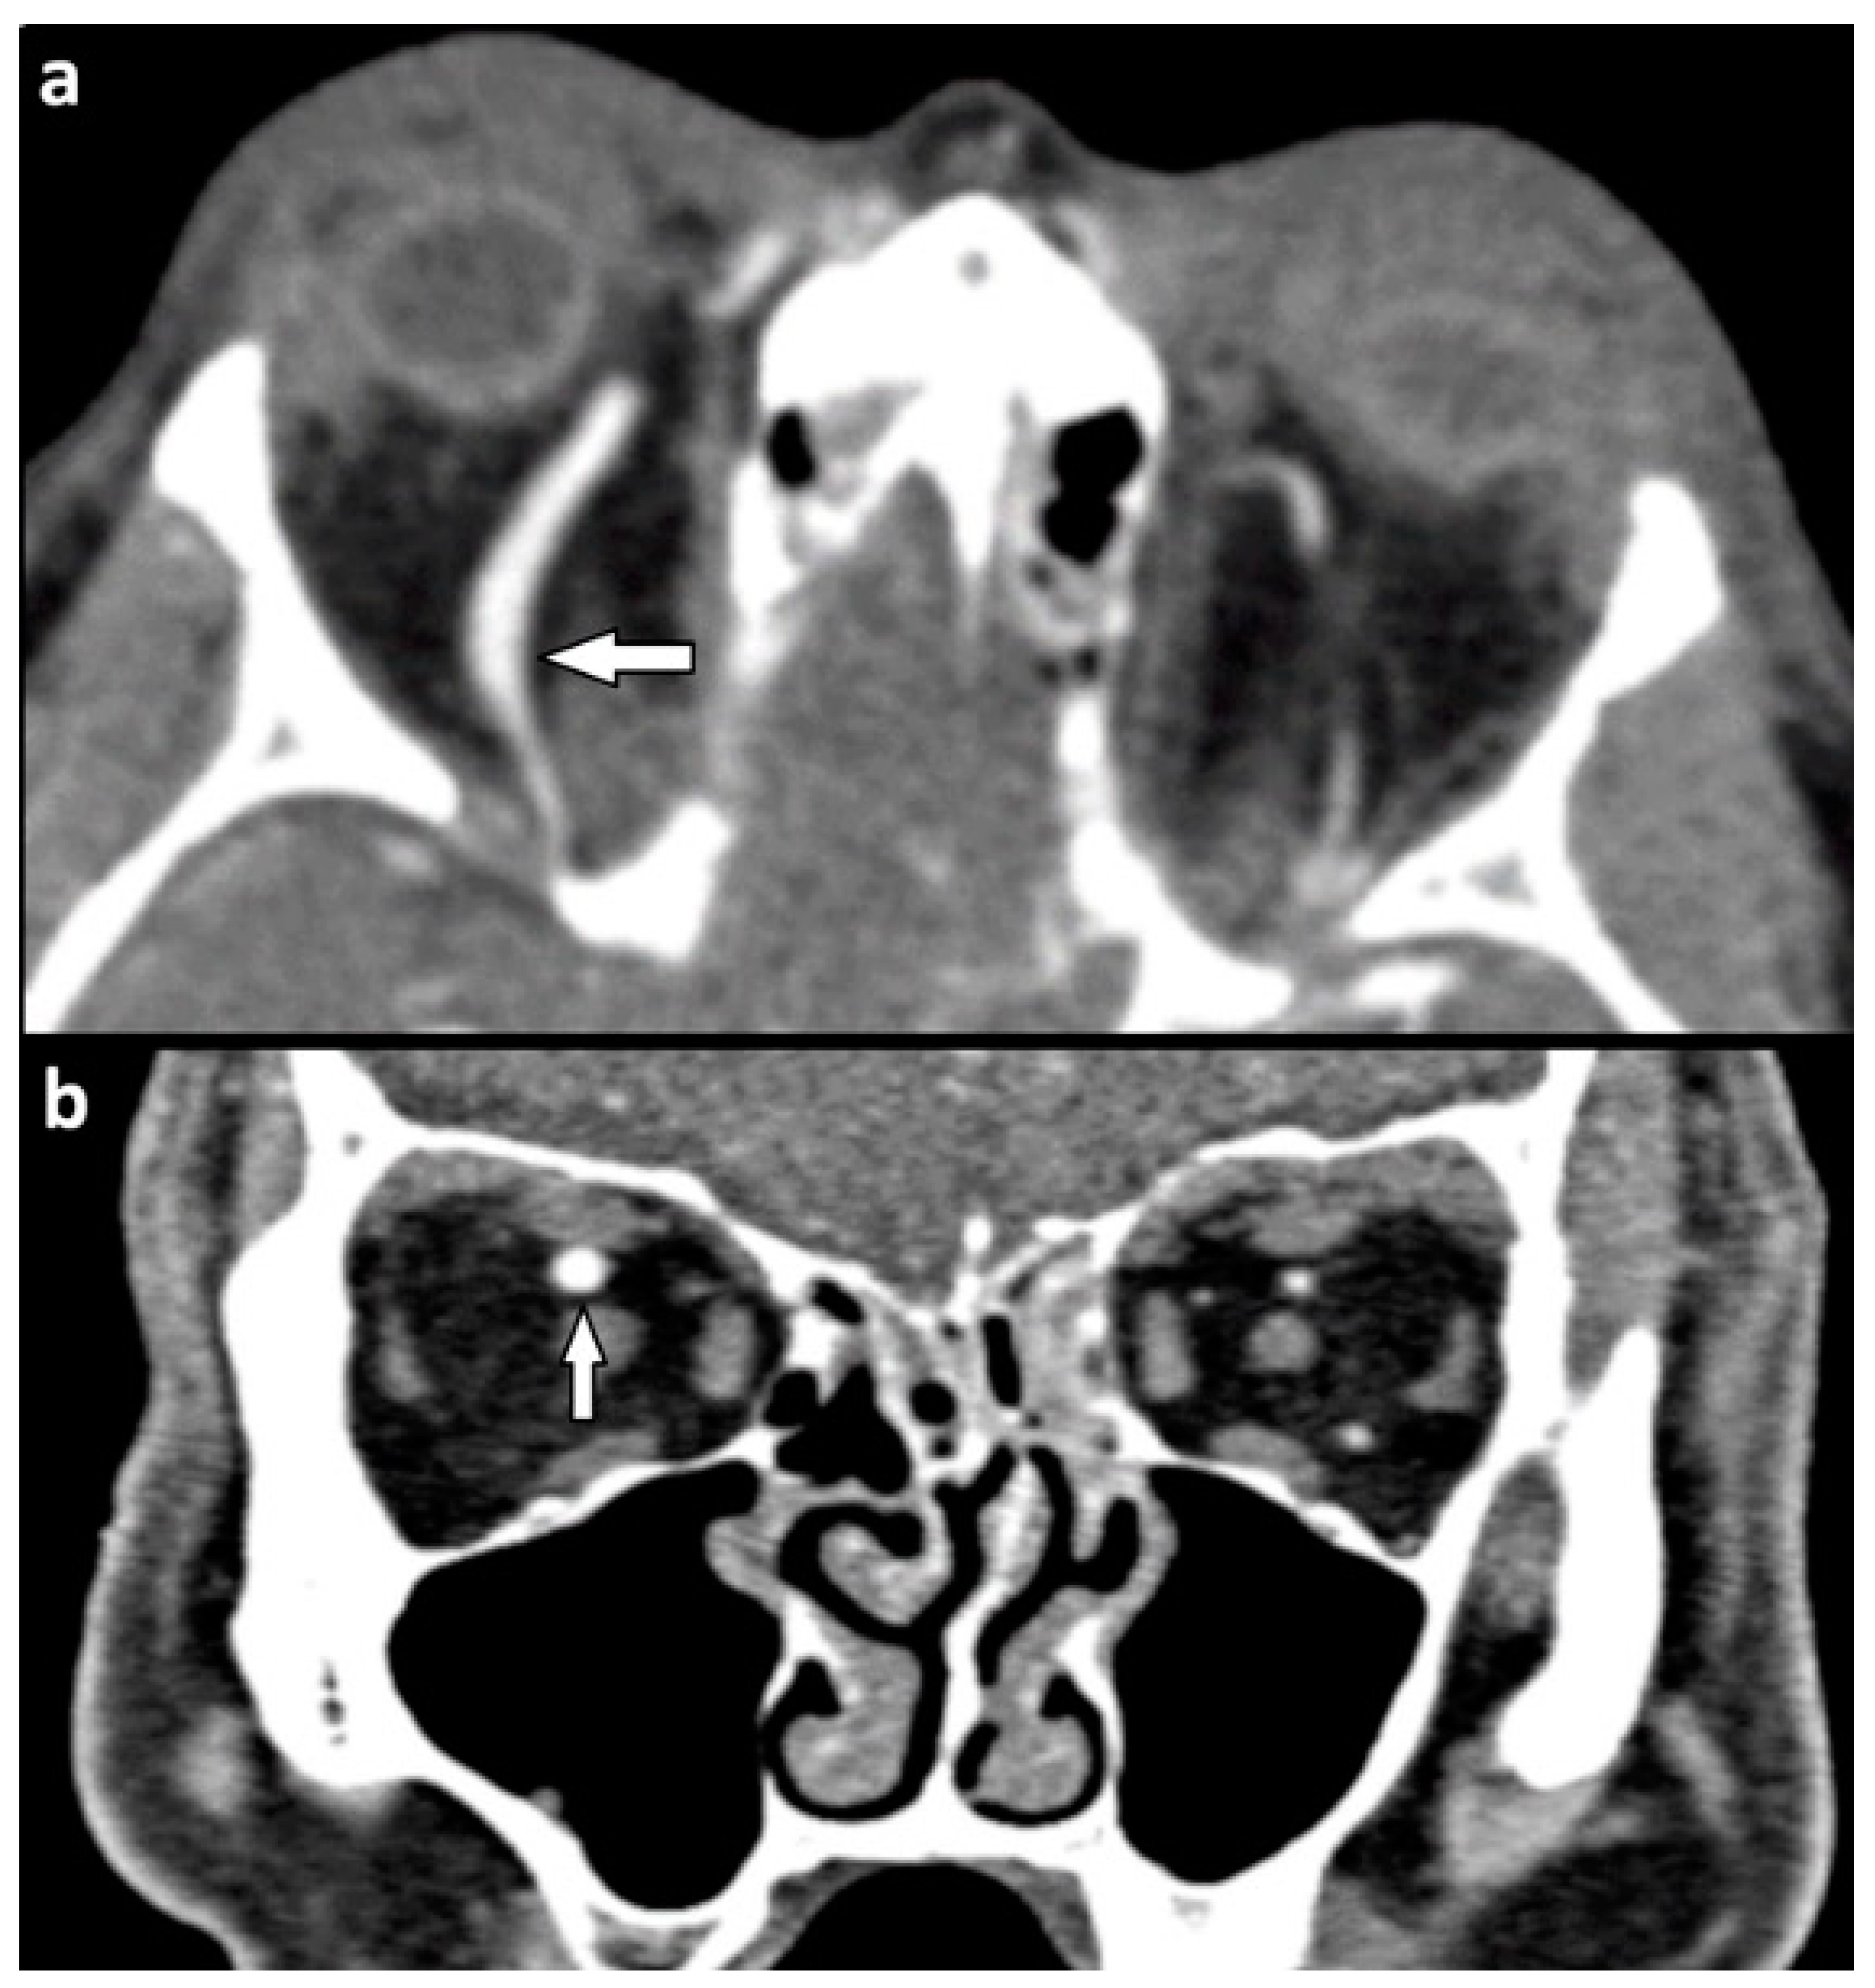

| Orbital vessels | 16 (15.8) | |

| dilated superior ophthalmic vein | 10 (9.9) | |

| direct carotid cavernous fistula | 6 (5.9) |